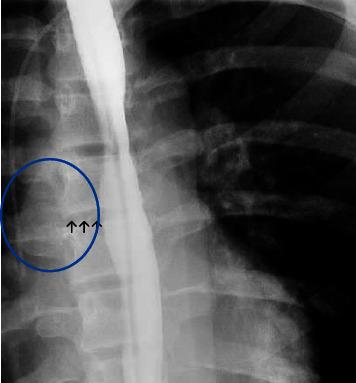

一名青少年自发性食管穿孔后发生脑脓肿。

Brain Abscess due to after Spontaneous Esophageal Perforation in an Adolescent.

is an inhabitant of the oral cavity and gastrointestinal tract, known to cause deep-seated abscesses. Thereby, we present a previously healthy adolescent with esophageal perforation (EP) and secondary mediastinal and brain abscesses due to . EP is a potentially life-threatening condition that requires a prompt diagnosis.

摘要

是口腔和胃肠道的寄居菌,已知可引起深部脓肿。因此,我们报告一名既往健康的青少年,因……导致食管穿孔(EP)以及继发性纵隔和脑脓肿。EP是一种潜在的危及生命的疾病,需要及时诊断。